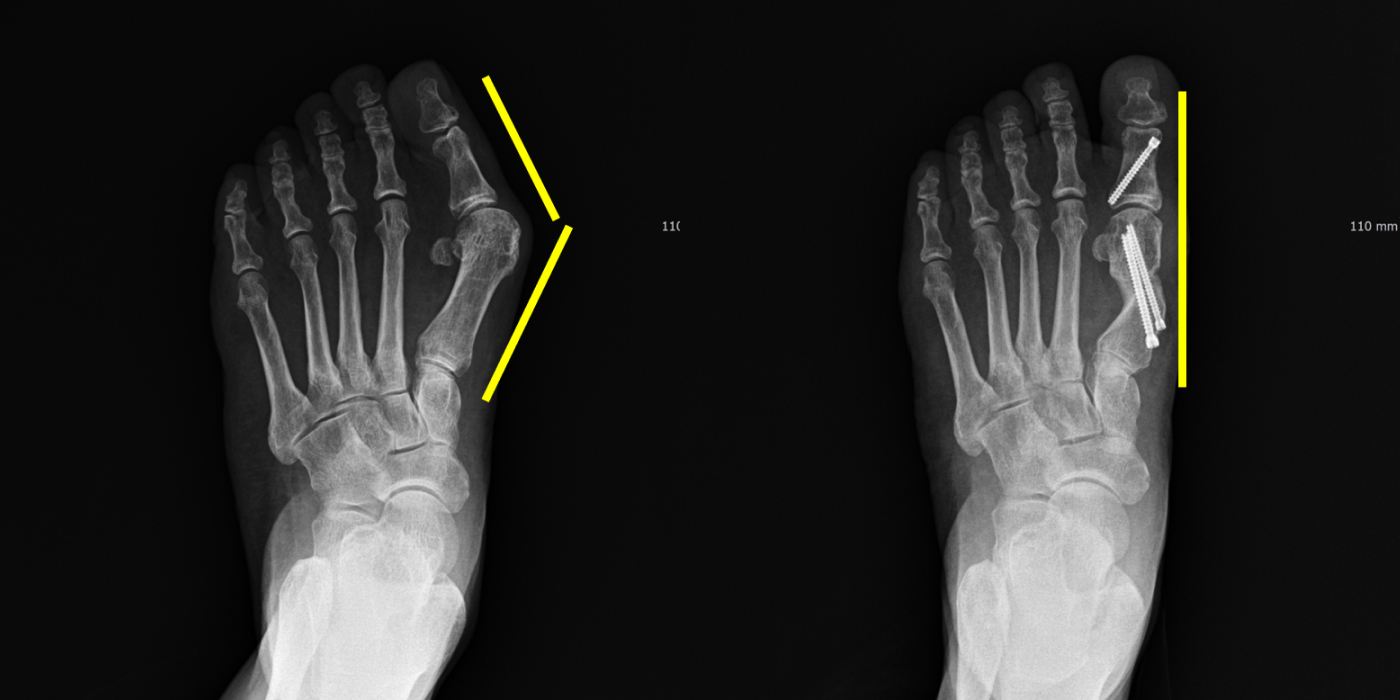

A+ 4세대 최소 흉터 무지외반증 수술

A+ 4세대 최소 흉터

무지외반증 수술은

2~3mm 절개로 뼈 교정,

통증은 줄이고 흉터는 거의 없습니다.

A+MITA(Minimal Invasive Transverse Akin)

수술은

엄지발가락 휘어짐을 교정하는

최소침습 수술법입니다.

2~3mm 미세한 구멍만으로 뼈를 자르고,

특수 나사로 정밀 고정하여

통증과 흉터를 최소화합니다.